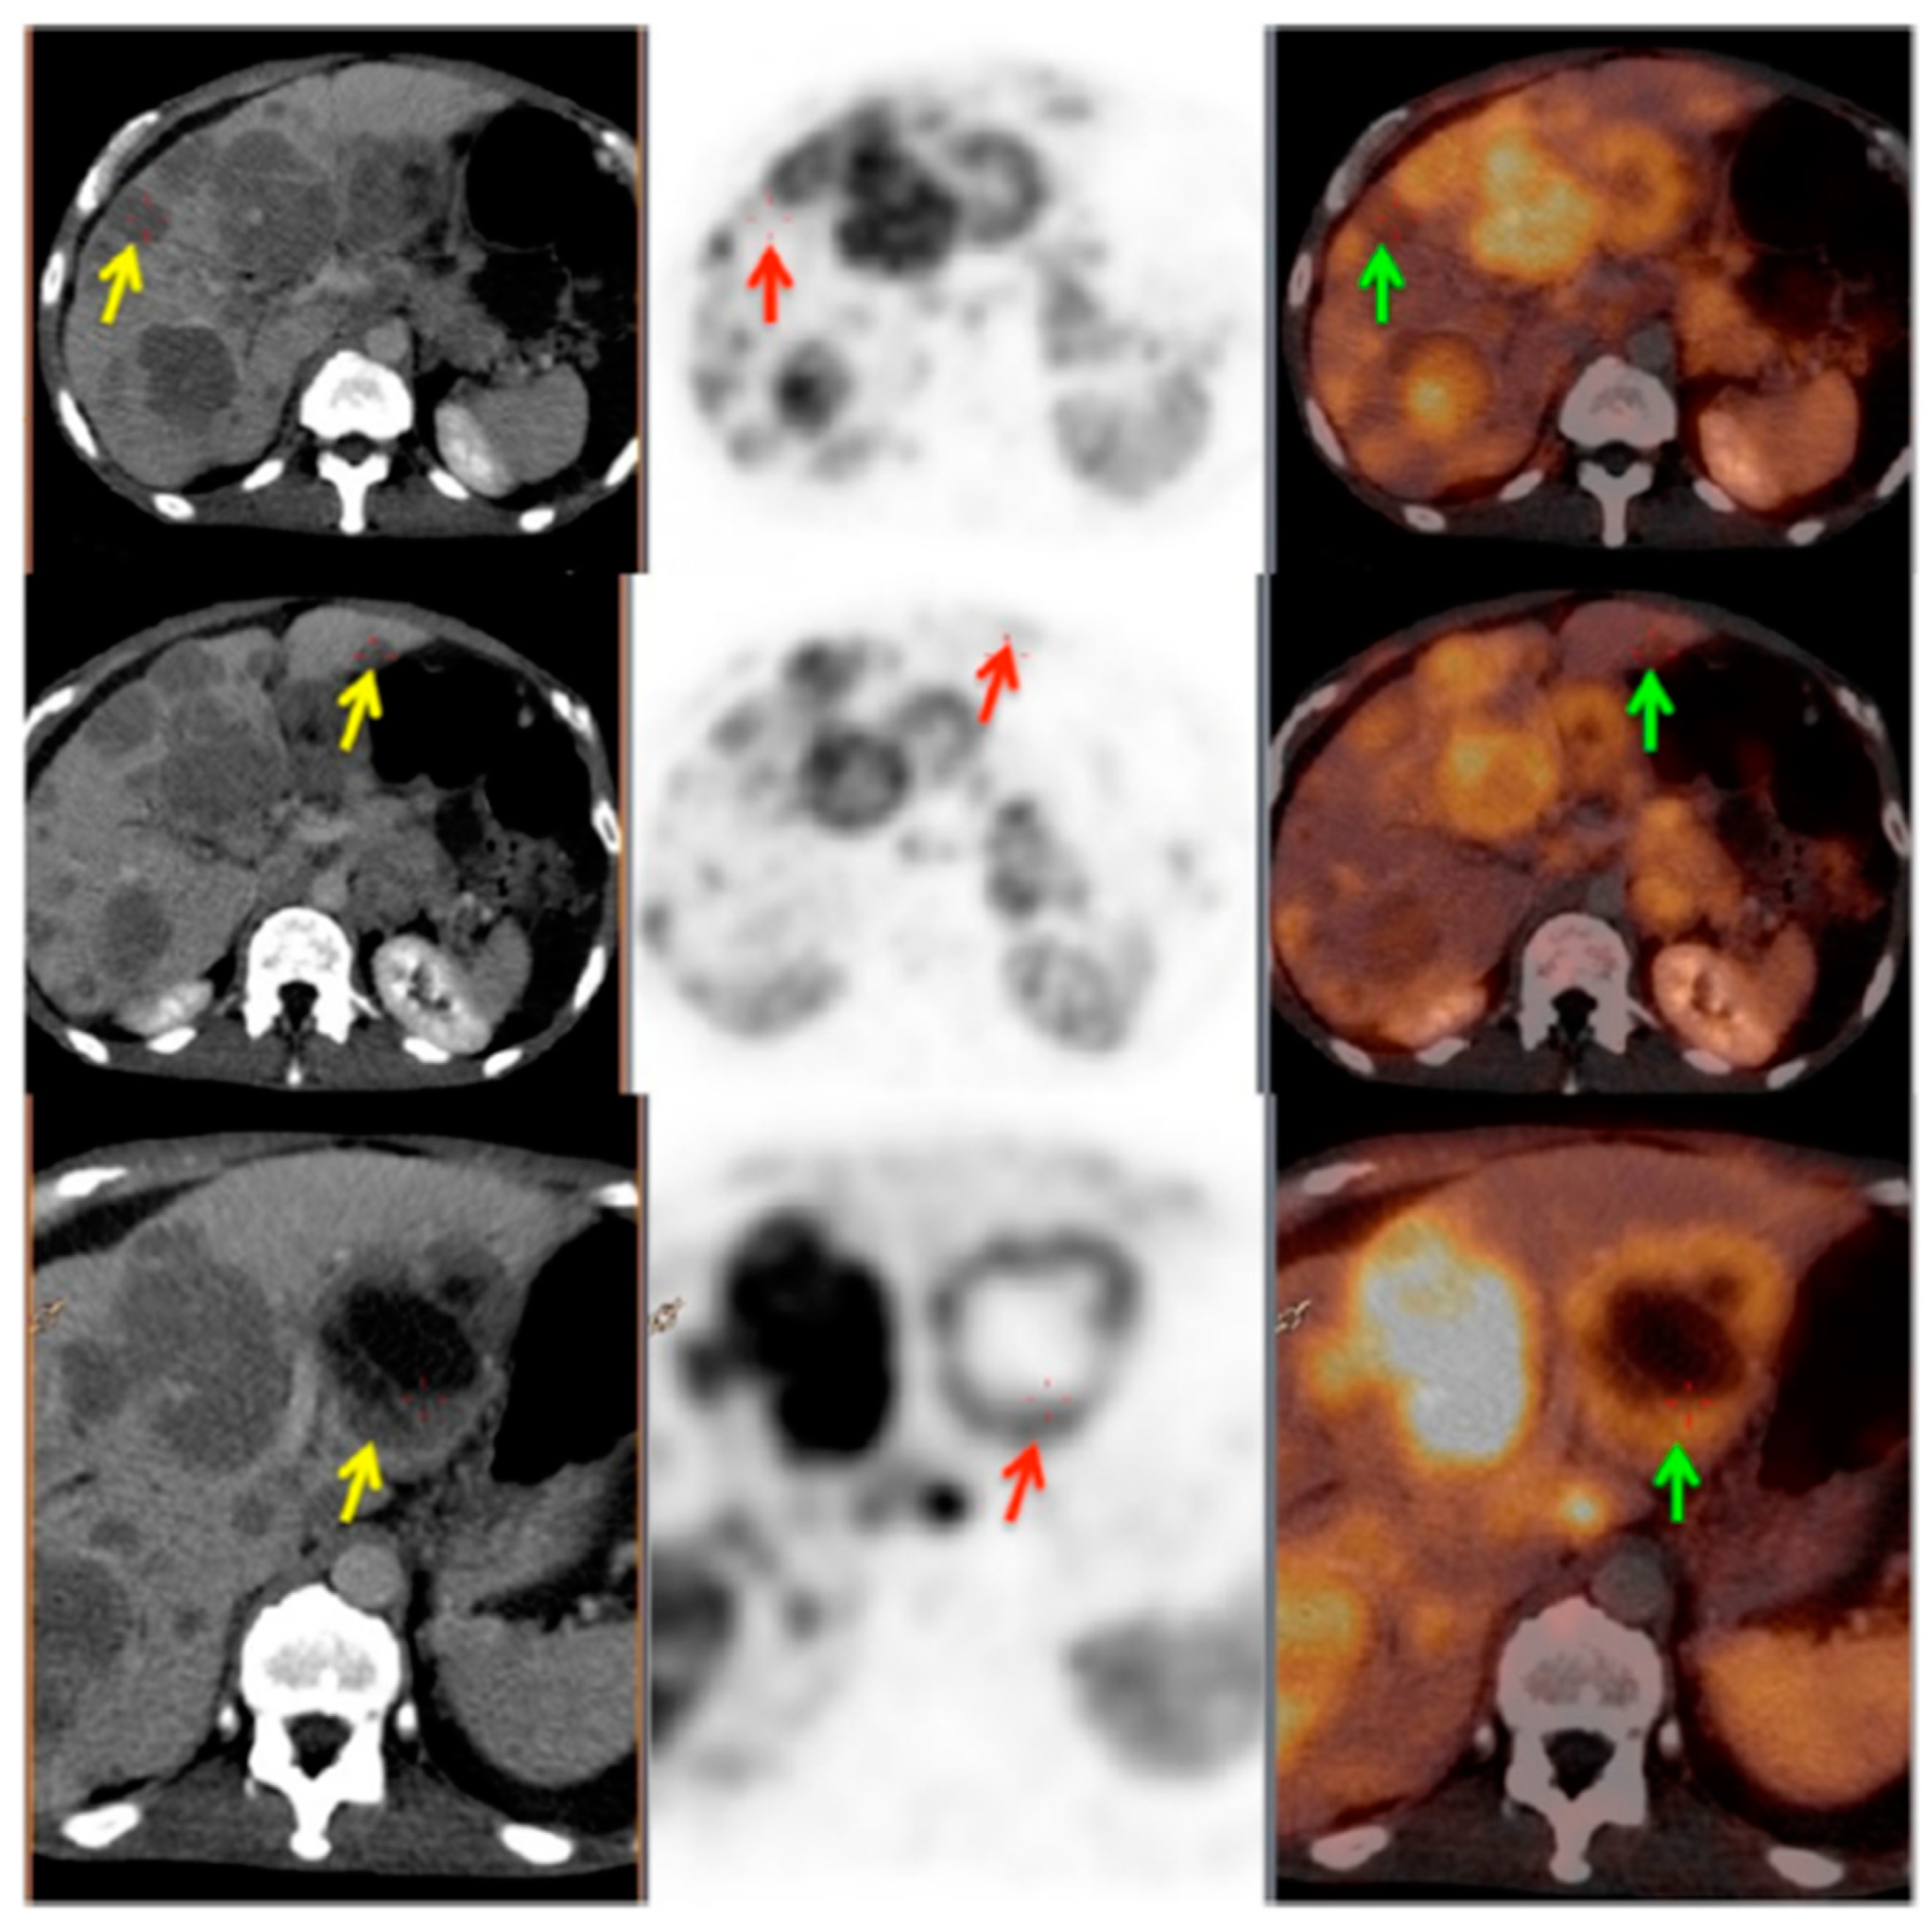

Figure 3.

PET/CT image showing somatostatin receptor heterogeneity. Left panel: CT images; middle panel: PET images; right panel: PET/CT fused images. Yellow arrows show the CT lesions in liver; red and green arrows show corresponding lesions on PET and PET/CT fused images, respectively. This patient was characterized as heterogeneous as more than 50% of the target lesions showed heterogeneous somatostatin receptor (SSTR) expression. Reproduced from [104].